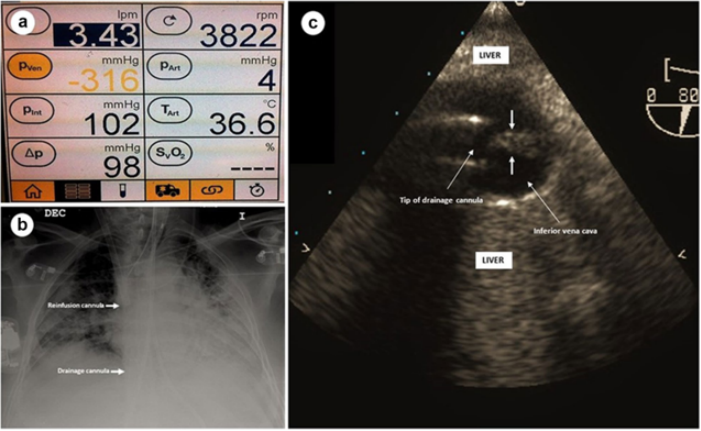

(1)流量下降:通过心脏超声和肺部超声协助评估引起流量下降的原因,例如容量不足、插管位置改变、插管附近血栓形成、张力性气胸、胸腔积液或心脏填塞时胸腔内压力增高等。图3为文献报道的甲流患者在VV-ECMO第8天时,发现其流量有明显下降,引流端压力已经低至-316 mmHg。胸片提示插管位置正常,而通过TEE发现下腔静脉内血栓位于ECMO引流管的尖端开口处,从而引起流量不稳定。

图片

图3  TEE示下腔静脉内血栓位于ECMO引流管尖端开口处

注:TEE:经食管超声心动图。